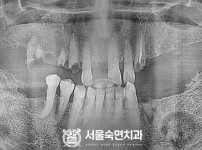

임플란트-전후사진1